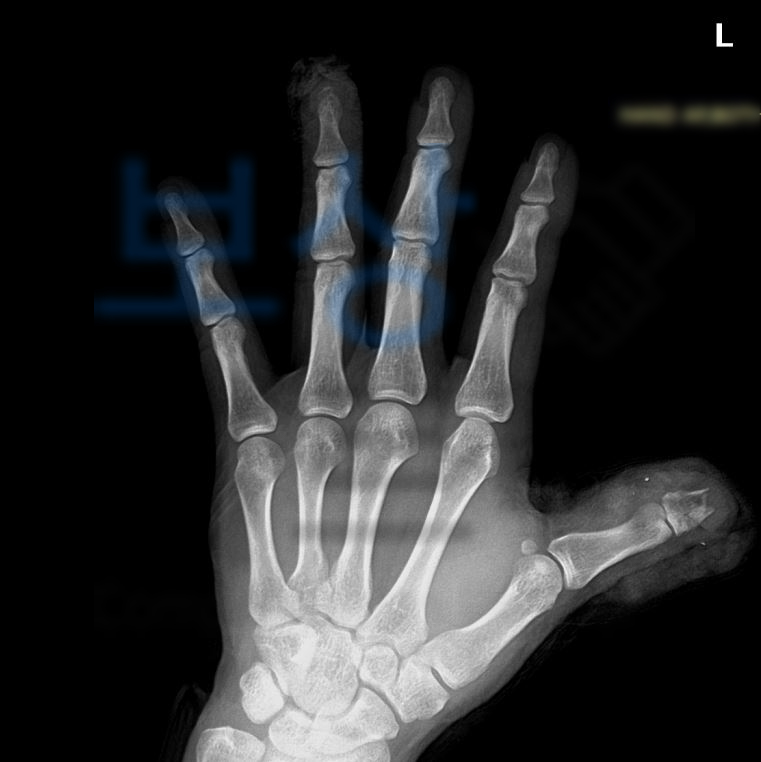

위 의무기록을 보시면 왼손의 첫째 손가락 즉 엄지손가락 뿐만 아니라

두 번째, 세 번째, 네 번째 까지… 통증을 호소하시고 골절되신 부분 확인됩니다… 내 보험증권에서 "후유장해” 항목을 찾아보세요. 의뢰인은 보험증권을 분석한 결과